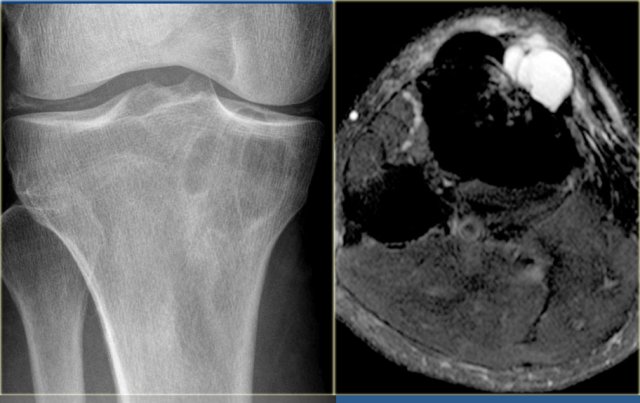

Young patient with a lobulated lytic lesion within the anterior cortical bone of the proximal tibia.

There is a second lucency separately more proximal within the cortical bone.

Axail CT image prior to biopsy demonstrates the lytic appearance of the lesion within the thickened cortical bone.

In the differential diagnosis could have been chondromyxoid fibroma or fibro-osseous lesion, however, the separate cortical lesion strongly suggests adamantinoma, which is almost exclusively found in the tibia and often multicentric.